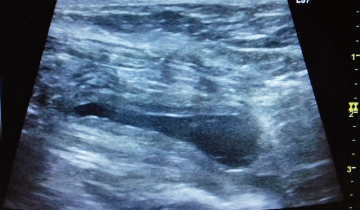

血尿を主訴に来院したプードルです。レントゲン検査と超音波検査で膀胱結石と診断しました。

矢印で示したのが結石です。

手術では膀胱を切開し、無事結石を全て摘出しました。

術後のレントゲン検査と超音波検査で結石が取り切れているのを確認。術後経過は良好で血尿も治まり退院しました。